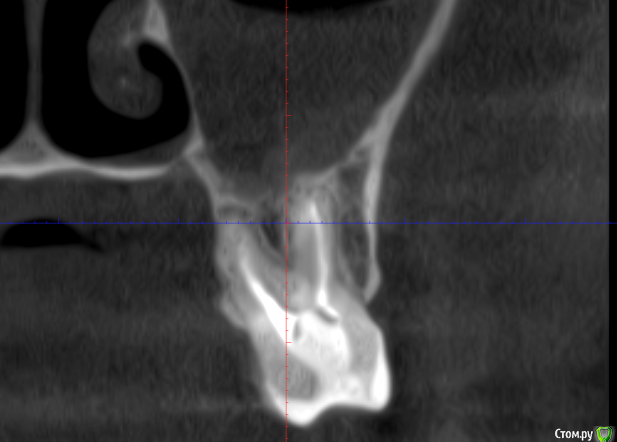

It'sGeorgy Опубликовано 11 декабря, 2019 Поделиться Опубликовано 11 декабря, 2019 (изменено) Всем здравствуйте! Слишком много проблемных пазух сыпется на меня в последнее время. Пациентку в лицо впервые увижу в пятницу, обратилась в клинику с жалобами "пол головы болит, сделайте что-то, мне в отпуск через месяц" . По телефонному разговору удалось разузнать: лежала в неврологии 3 месяца назад, где обострился гайморит. Там отправили к ЛОРами, те назначили антибиотики и сказали делать "кукушку", там же сделали КТ(в приложениях). После этого, пошла по ДМС к другому ЛОРу, показала КТ. Сказали, причина в восьмерке. Восьмерка полностью ретенирована(Со слов пациентки, опять же, сам не видел еще). Корень в пазухе(?). - прикрепленное 1.Рядом находится 2.7 с незапломбированным мб2 - прикрепленное 2. И недопломбированным небным корнем + воспаление на этом корне. - прикрепленное 3.Пазуха - прикрепленное 4. https://cloud.mail.ru/stock/bky4cB7brg4DmMjaY7NSGR7y - KT + MPT. Открывается винраром. На перелечивание 2.7 зуба пациентка может не согласиться. Удалять ли 2.7 зуб? Может ли ТОЛЬКО полностью ретинированная восьмерка вызвать подобное состояние пазухи или искать что-то еще? Изменено 11 декабря, 2019 пользователем It'sGeorgy Ссылка на комментарий